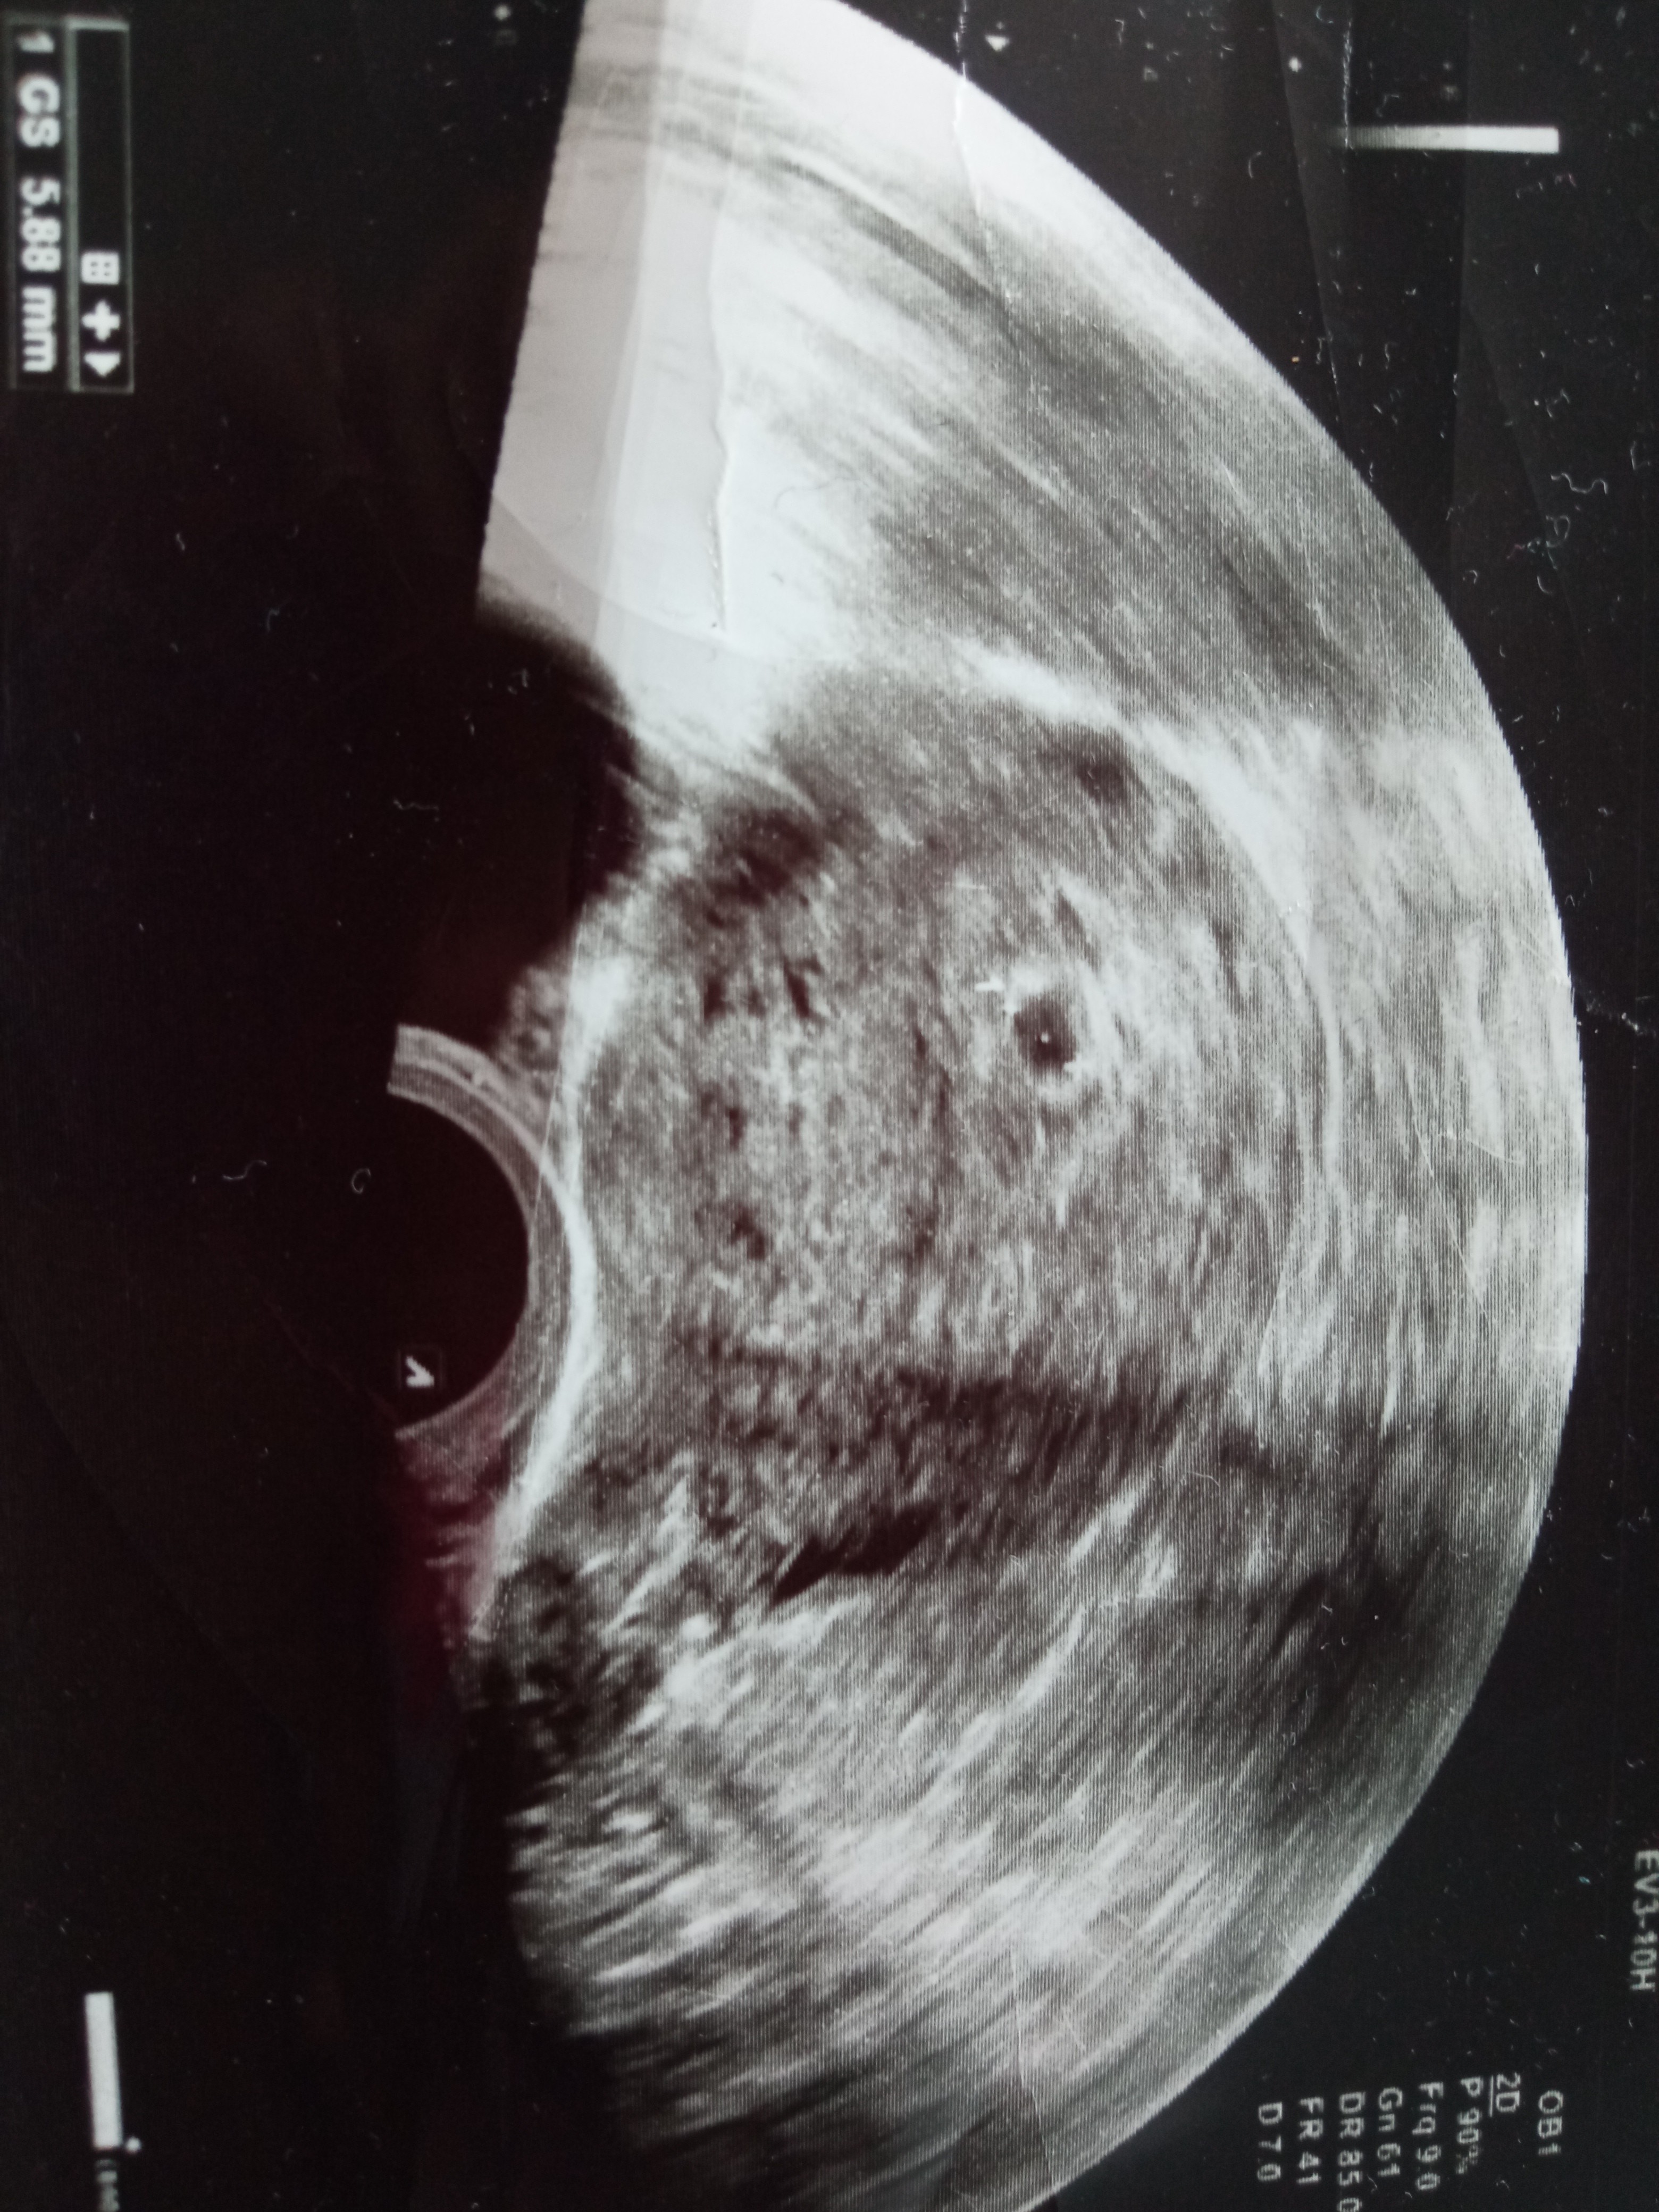

Cześć dziewczyny, chciałabym was prosić o poradę , a mianowicie byłam na USG 5 tydzień , lekarz nie odpowiedział na moje pytania zrobił USG i do widzenia , oczywiście zarejestrowałam się do innego za 2 tyg wizyta . Czy na USG widać tylko pęcherzyk czy cos jest w pęcherzyku? Z góry dziękuję za odpowiedzi.

Też uważam, że pęcherzyk, co w 5 tygodniu jest obrazem prawidłowym.

Pęcherzyk żółtkowy pojawia się między 5+2 a chyba 5+5.